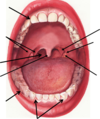

label the diagram

frontal region/ orbital region/ partiod region/ nasal region/ buccal region/ oral region/ mental region

label the diagram:

ascending pharyngeal/ occipital/ posterior auricular/ maxillary/ facial/ lingual/ superthyriod/ superficial temporal/